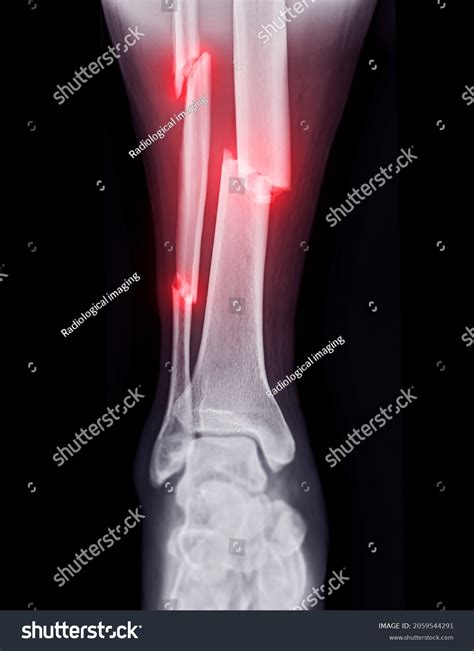

While some minor fractures may feel manageable, you should seek a broken ankle Xray immediately if you observe "red flag" symptoms. Delaying imaging can lead to improper healing, chronic pain, and future joint instability. Indicators for an emergency visit include:

• An obvious deformity where the ankle appears bent or out of place.

• Bone protruding through the skin (an open fracture), which is a medical emergency requiring immediate surgery.

• Numbness, tingling, or the foot turning pale or blue, indicating potential nerve or blood vessel damage.

• The inability to move your toes, which can signal significant trauma near the ankle joint.